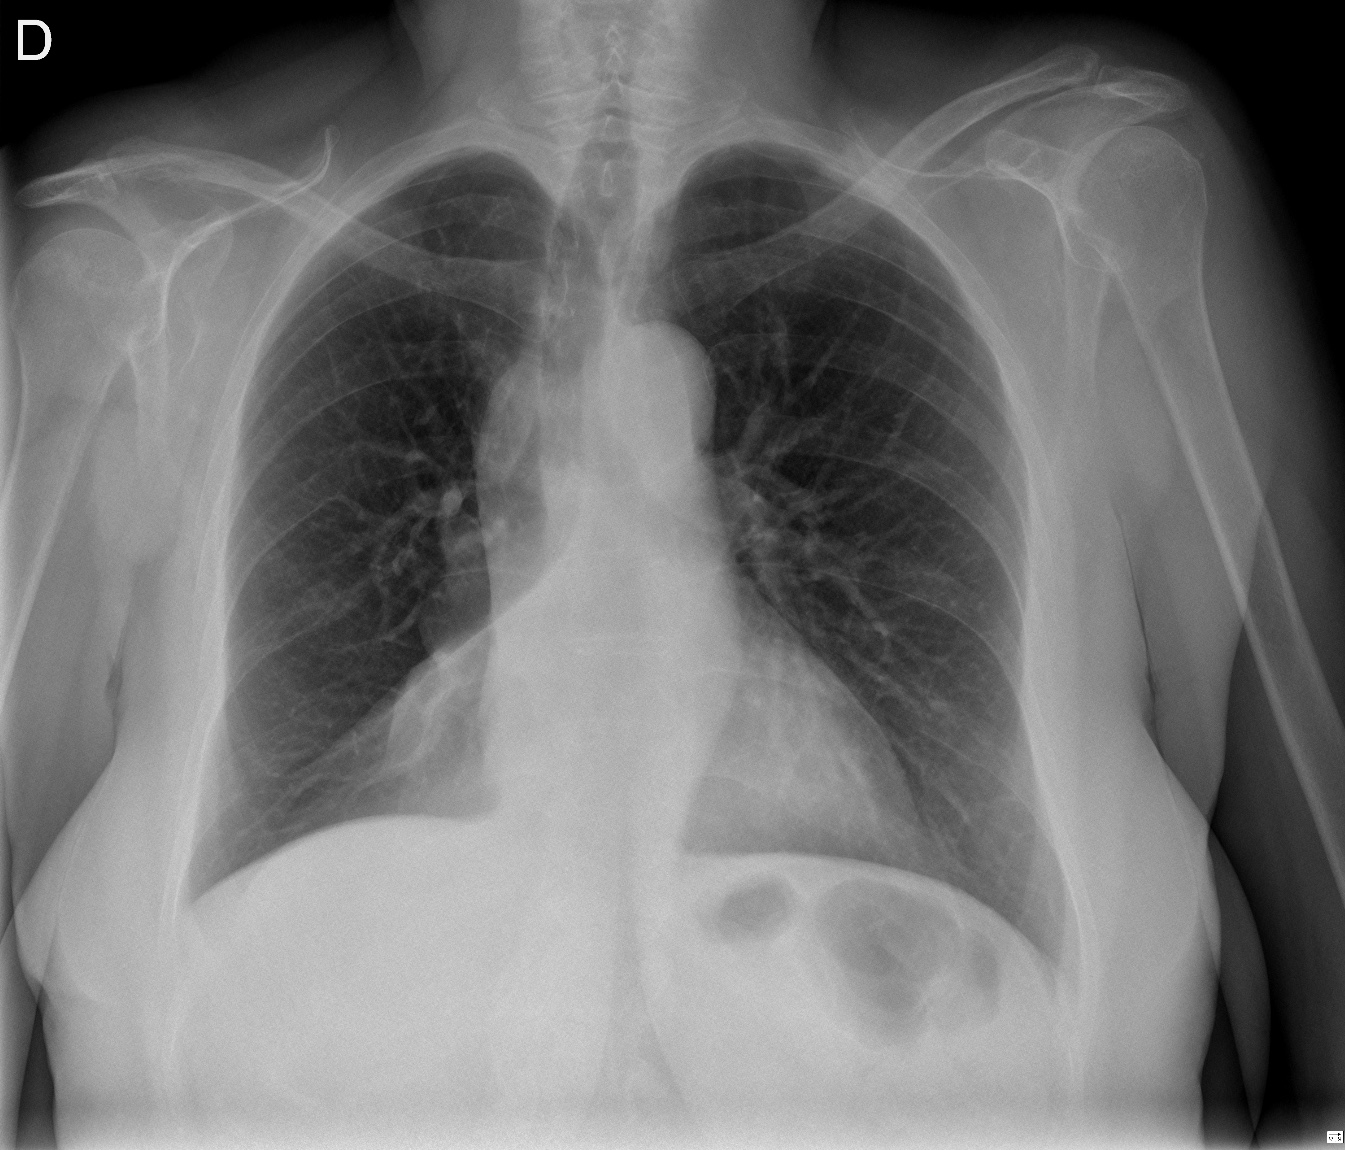

CASO: Revisión.

Hallazgos:

- Mastectomía derecha.

- Resto del estudio sin hallazgos de significación.

RECUERDA LA SISTEMÁTICA PARA NO OLVIDAR NINGUN HALLAZGO. A esta paciente le han extirpado la mama derecha, motivo por el cual se observa una asimetria entre las densidades de las bases pulmonares.